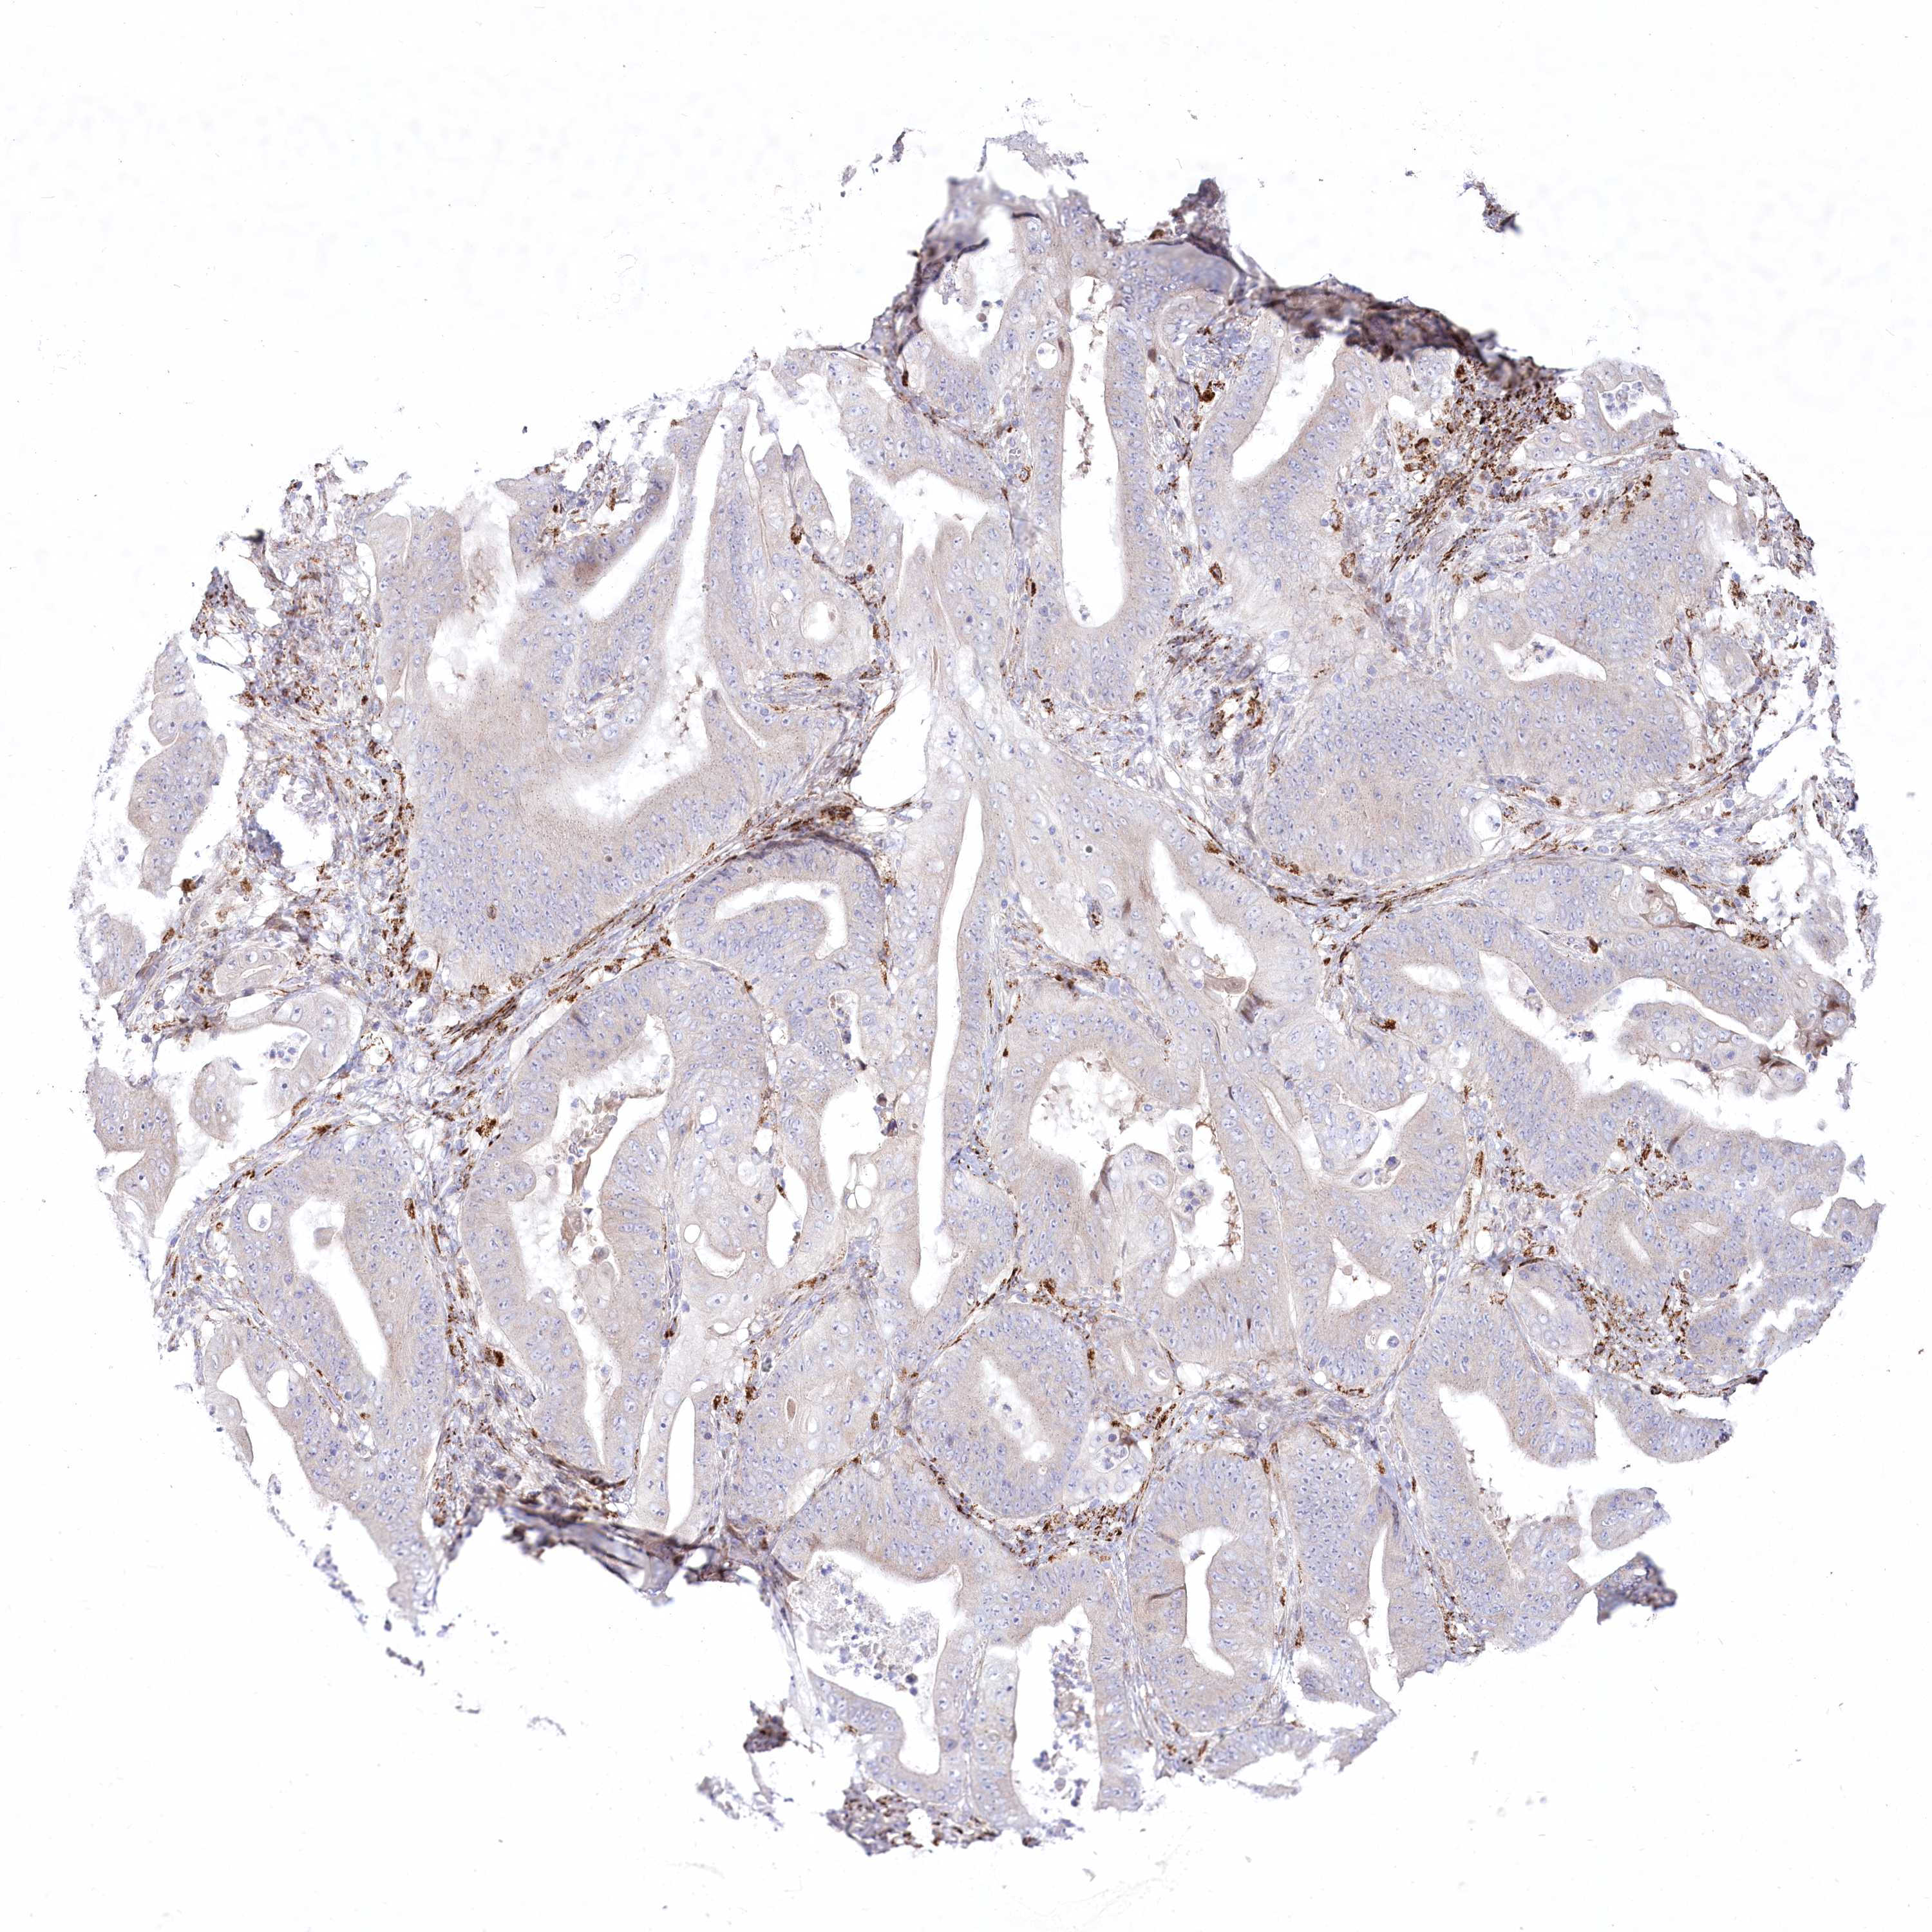

STOMACH CANCER - Protein expressioni

A mouse-over function shows sample information and annotation data. Click on an image to view it in a full screen mode. Samples can be filtered based on level of antibody staining by selecting one or several of the following categories: high, medium, low and not detected. The assay and annotation is described here.

Note that samples used for immunohistochemistry by the Human Protein Atlas do not correspond to samples in the TCGA dataset.

Antibody stainingi

Antibody staining in the annotated cell types in the current human tissue is reported as not detected, low, medium, or high, based on conventional immunohistochemistry profiling in selected tissues. This score is based on the combination of the staining intensity and fraction of stained cells.

Each image is clickable and will lead to virtual microscopy that enables deeper exploration of all samples and also displays staining intensity scores, fraction scores and subcellular localization as well as patient and tissue information for each sample.

Antibody HPA037605

Antibody HPA037606

Staining

High

Medium

Low

Not detected

Intensity

Strong

Moderate

Weak

Negative

Quantity

>75%

75%-25%

<25%

None

Location

Nuclear

Cytoplasmic/membranous

Cytoplasmic/membranous,nuclear

Adenocarcinoma, NOS